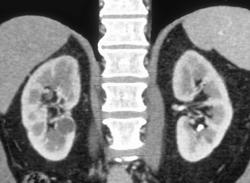

End Stage Kidney Disease (chronic Pyelonephritis)